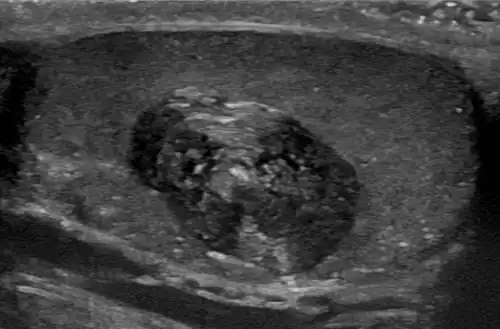

An epidermoid cyst or epidermal inclusion cyst[1] is a benign cyst usually found on the skin. The cyst develops out of ectodermal tissue. Histologically, it is made of a thin layer of squamous epithelium.

Epidermoid cysts are usually diagnosed when a person notices a bump on their skin and seeks medical attention. The definitive diagnosis is made after excision by a pathologist based on microscopic appearance of a cystic lesion lined by cornified epithelium containing lamellated keratin without calcifications. They can also be seen as isointense lesions on MRI or hyperintensities on FLAIR.